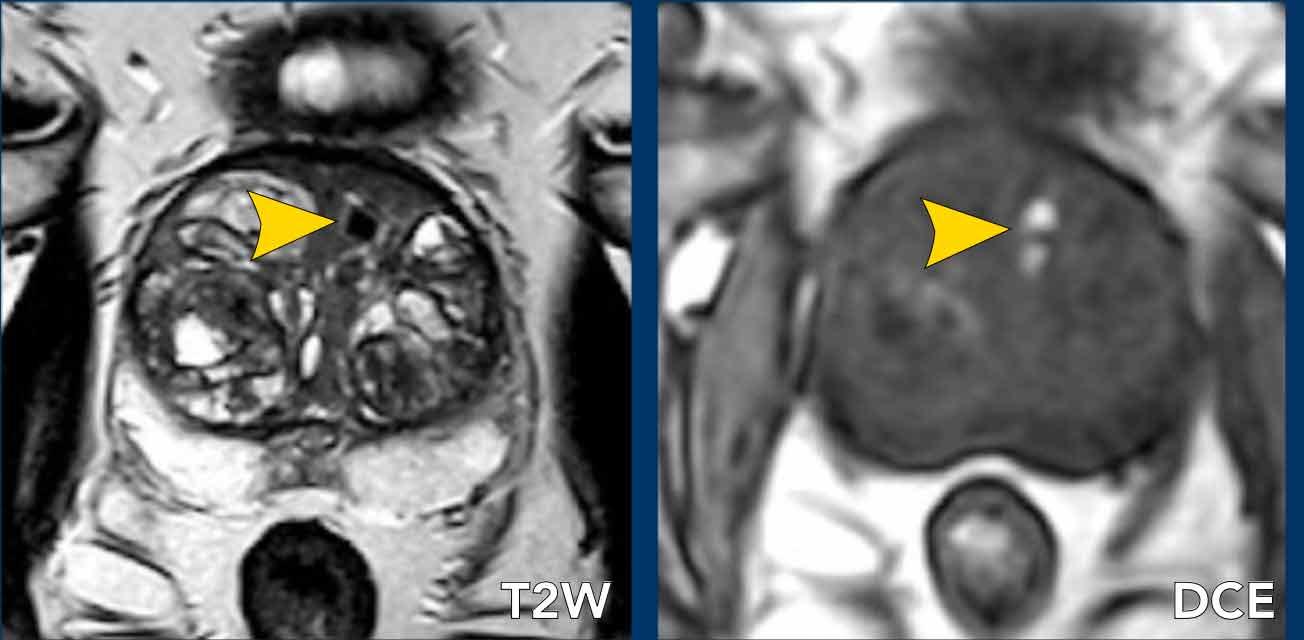

Bệnh nhân nam 70 tuổi được chuyển đến với PSA tăng 9ng/ml, mật độ PSA 0,10.

Điểm PI-RADS 5 được gán cho một vùng giảm tín hiệu ở vùng ngoại vi bên phải tại phần giữa tuyến, có hạn chế khuếch tán (mũi tên đen).

DCE cho thấy ngấm thuốc mạnh và ngoại vi của tổn thương (đầu mũi tên).

Sinh thiết được thực hiện và kết quả mô bệnh học cho thấy hình thành ổ áp xe.

Ngấm thuốc ngoại vi và hạn chế khuếch tán là những phát hiện hình ảnh điển hình của ổ áp xe.